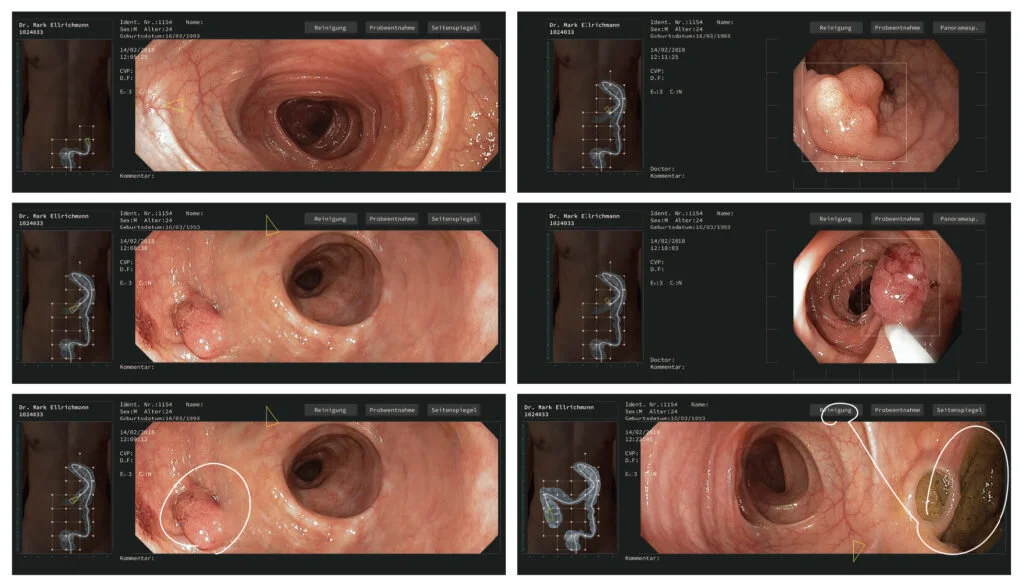

The next-generation endoscope with three cameras, real-time 3d modeling, a brand new controller, and an interface.

全新一代内窥镜,结合多摄像头、传感器实时建模、体内定位等多项全新技术,配合全新的手持设备及用户界面,打造未来无限可能。